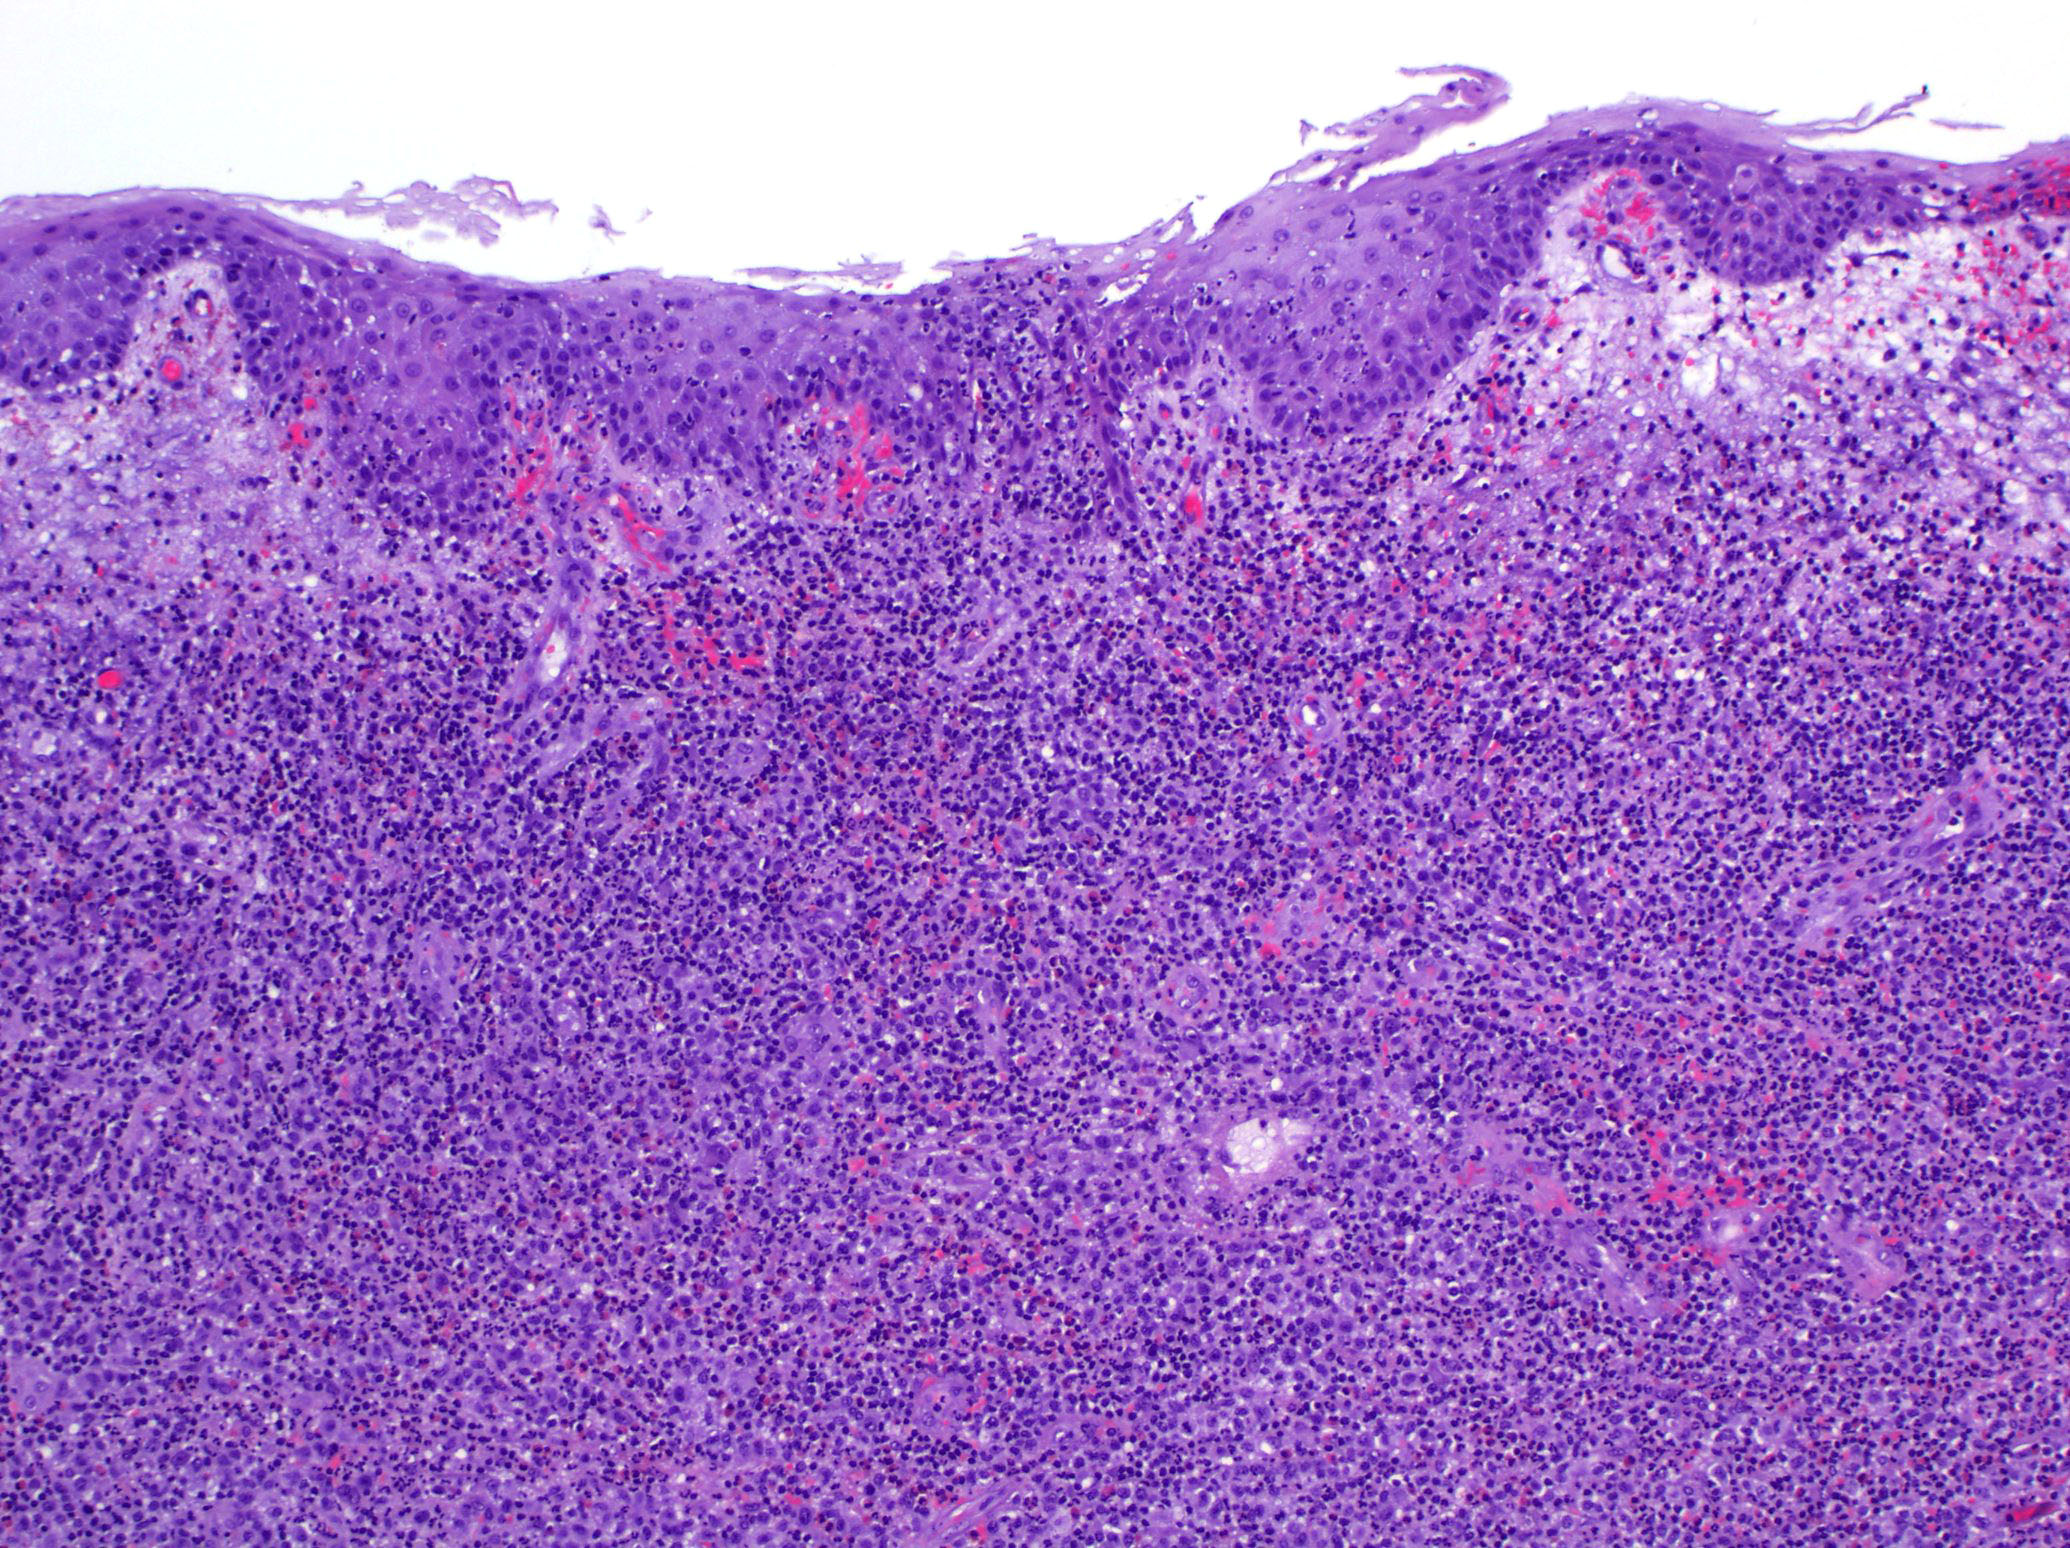

- Lymphomatoid papulosis is characterized by a wedge shaped pattern, with a wide superficial base and the tip at the bottom, usually deep dermis and less frequently into the subcutaneous tissue

- Type B: epidermotropism and band-like distribution of small to medium atypical lymphocytes with cerebriform nuclei, without CD30+ expression and mimics mycosis fungoides, patch stage

- Type D: atypical small to medium lymphoid infiltrate with epidermotropism; the neoplastic cells express CD30 and CD8 and mimic pagetoid reticulosis

Microscopic (histologic) images

Contributed by Roberto N. Miranda, M.D.